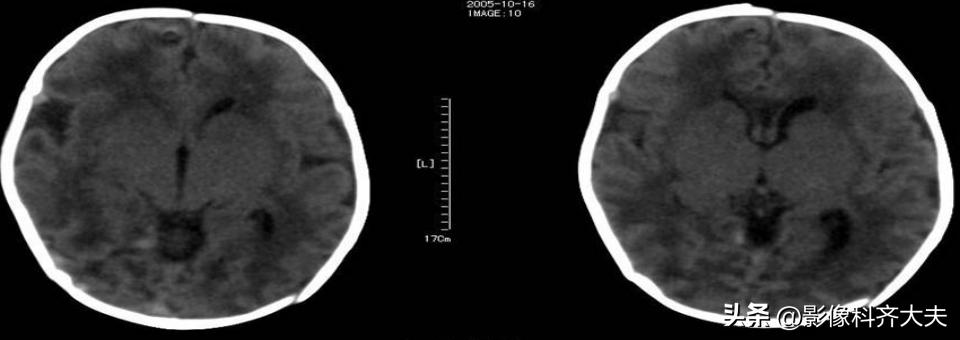

HIE的CT表现

1、测定脑实质的CT值,正常足月儿脑白质CT值在20Hu以上,≤18Hu为低密度

2、脑水肿时呈双侧大脑半球呈弥漫性低密度伴脑室变窄

3、基底核和丘脑损伤时呈双侧对称性高密度影

4、脑梗死表现为相应供血区呈低密度

CT分度

1、轻度:散在局灶低密度影分布2个脑叶内。

2、中度:低密度影超过2个脑叶,白质灰质对比模糊。

3、重度:弥漫性低密度影,灰质白质界限消失,但基底节、小脑尚有正常密度。

注:中、重度常伴有颅内出血。